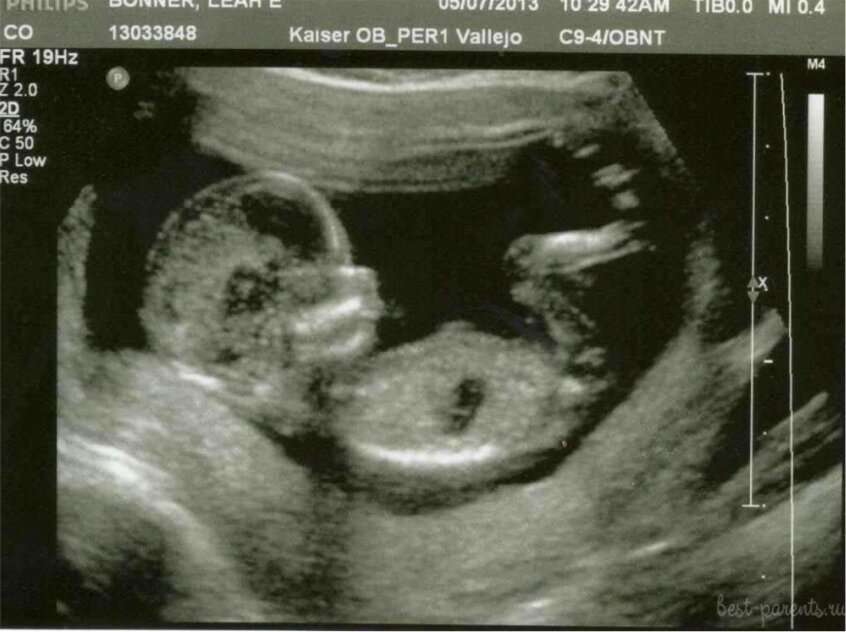

И вот датчик скользит по округлившемуся животу. Сомнений нет, срок солидный, плюс/минус двадцать недель.

Специалист повернула монитор с изображением плода в утробе. Оправившись от шока, пациентка растерянно пролепетала: «Да я ж таблетки пила! Импортные, дорогие, в интернете заказывала! На форуме про них такие отзывы, 100%-ная гарантия результата… Получается, ребёнок в животе? А я боялась, что это опухоль шевелится! Думала, у меня рак…»